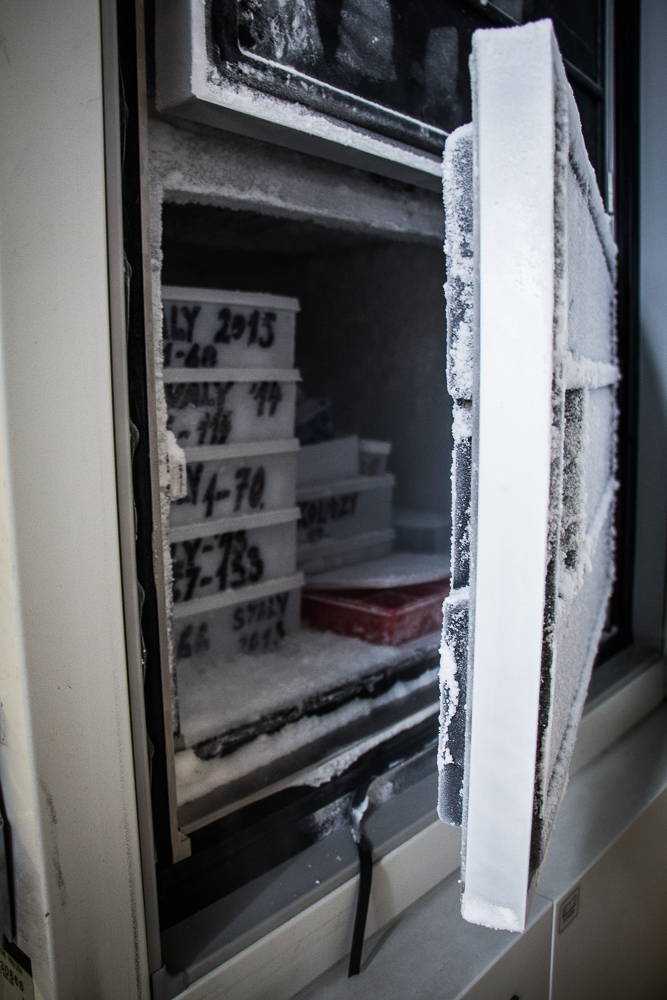

Ústav patologie a molekulární medicíny se zabývá komplexní laboratorní diagnostikou nádorových a nenádorových onemocnění. Využívá metod klasické histologie a cytologie s navazujícími dalšími speciálními laboratorními vyšetřovacími metodami. Ty zahrnují: pohled do buněk a tkání na úrovni ultrastrukturální analýzy (elektronová mikroskopie), průkaz exprese proteinů (metody imunohistochemické, Western blot, průtoková cytometrie), průkaz enzymové aktivity ve tkáňových řezech (enzymová histochemie), analýzu změn na úrovni chromozómů a genů a průkaz některých virů v histologickém řezu (metody in situ hybridizace) a rozbor DNA a RNA extrahovaných ze tkání (metody kvalitativní a kvantitativní polymerázové řetězové reakce, sekvenování). Vyšetřovaným biologickým materiálem jsou tkáně (nativní, zmrazené, fixované), punktáty kostní dřeně, periferní krev, případně jiné buněčné tekutiny (výpotky) a autologní štěpy pro transplantaci kostní dřeně.